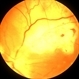

- Choroidal Melanoma

- Melanoma surrounded by laser.